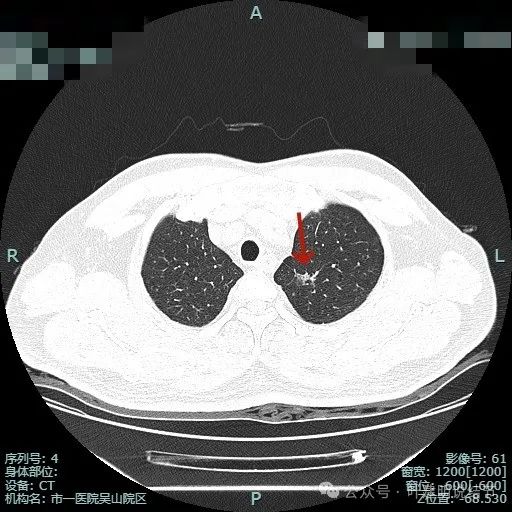

右上叶另有病灶B:微小淡磨,轮廓较清。

右肺另有微小实性结节,病灶C,考虑良性。

左上叶微小磨玻璃结节病灶D,有微小血管进入,但密度太低,风险极小。